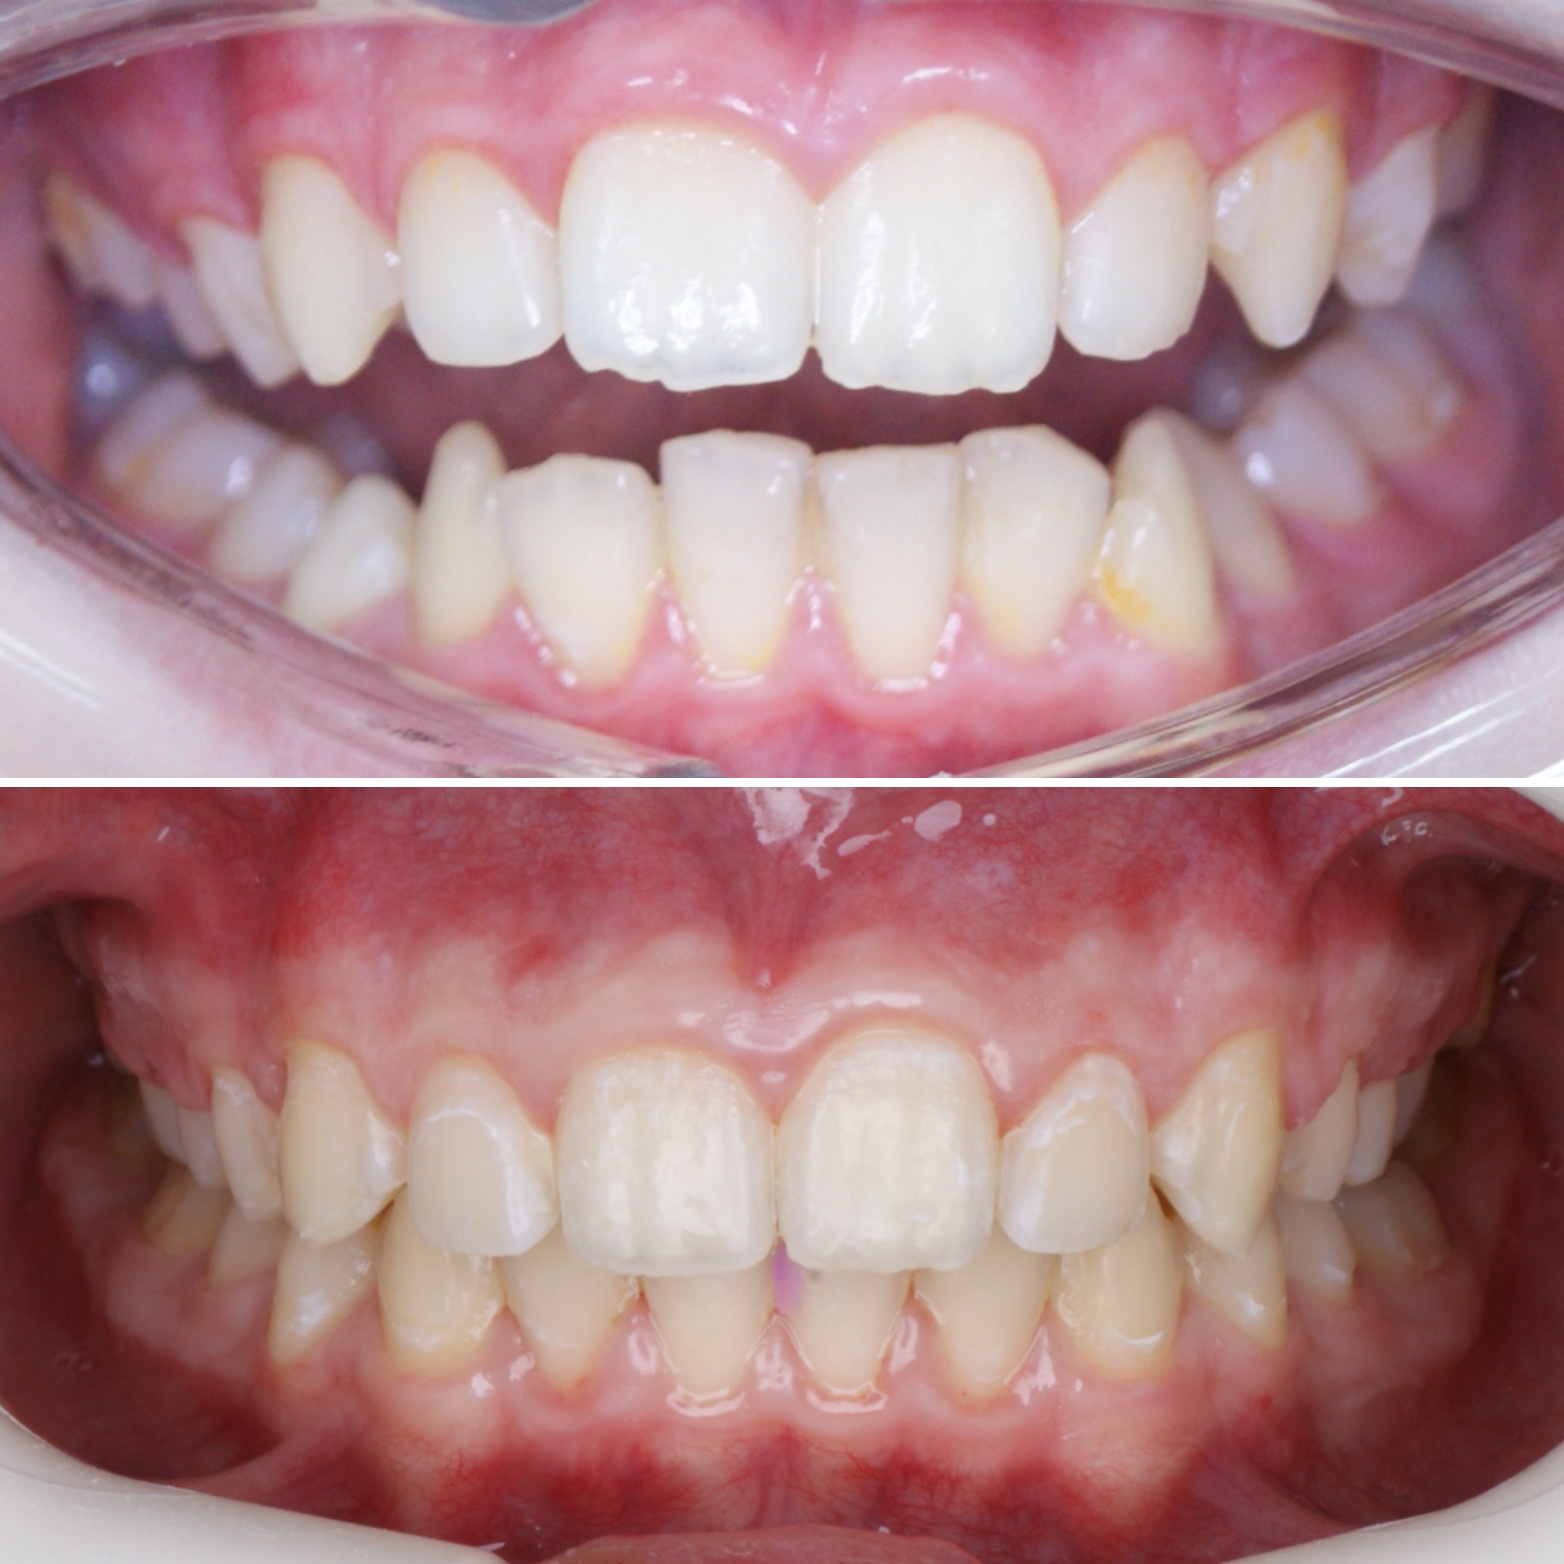

✔Глубокий прикус, дистальный прикус с пространством (щелью) между верхними и нижними резцами, скученное положение зубов, заблокированное нёбное положение верхнего левого зуба ✔Лечение на металлической самолигирующей системе Damon

✔Пациент, 12,5 лет на момент старта ✔Общий срок лечения 18 месяцев ✔Брекеты Damon Q ✔Дистальный, перекрестный, глубокий прикус, смещение нижней челюсти, несоответствие средних линий и сужение зубных рядов, скученность зубов, недостаток места для верхних клыков